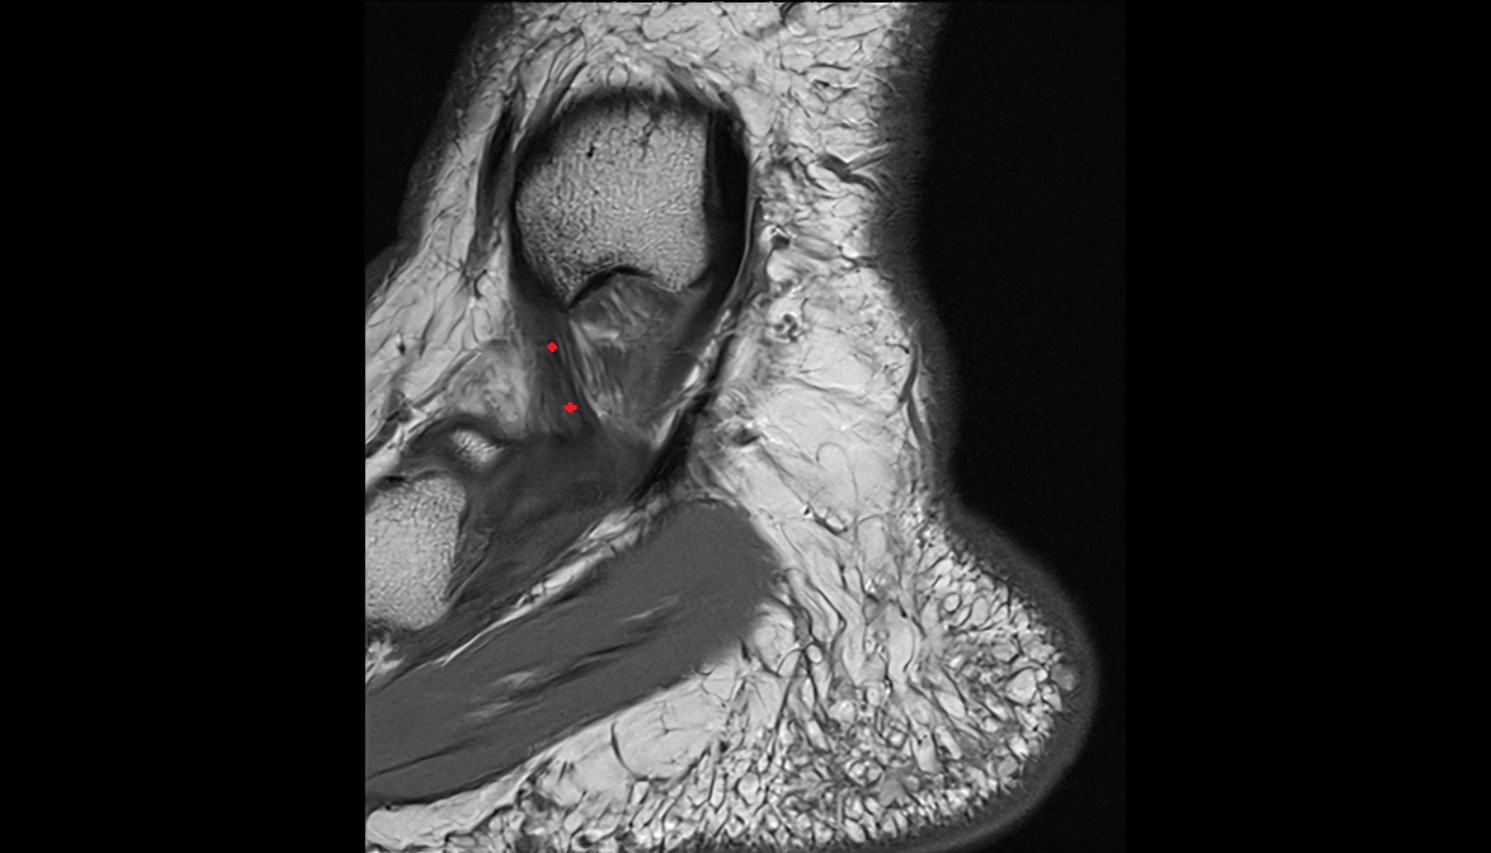

- Articular disc of temporomandibular joint

- Articular eminence

- Superior retrodiscal layer

- Superior synovial membrane of temporomandibular joint

- Temporomandibular joint

- Mandibular condyle

- Mandibular fossa